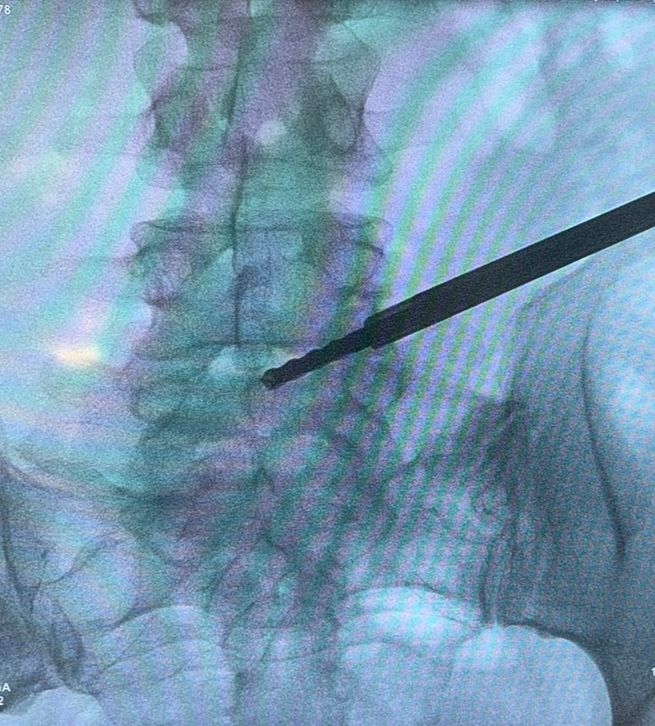

Starszy Asystent w Klinicznym Oddziale Neurochirurgicznym oraz Poradni Neurochirurgii Wojewódzkiego Szpitala Specjalistycznego im. św. Barbary nr 5 w Sosnowcu. Konsultant Kliniki Neurologii Szpitala Klinicznego nr 1 w Zabrzu. Absolwent Wydziału Lekarskiego Śląskiego Uniwersytetu Medycznego w Zabrzu. Staż podyplomowy odbył w latach 2010-2011 w Oddziale Neurochirurgii WSS nr 4 w Bytomiu. W 2018r. złożył egzamin specjalizacyjny po zakończeniu szkolenia w ramach rezydentury w WCM Opole. W 2019 roku uzyskał stopień doktora nauk medycznych. Specjalizuje się w kompleksowym leczeniu schorzeń kręgosłupa (dyskopatia, stenoza kanału kręgowego, kręgozmyk) oraz neuroonkologii. Szczególny zakres działań medycznych to nowoczesne, małoinwazyjne operacje kręgosłupa z wykorzystaniem technik endoskopowych (mikrodiscektomia - implanty rozprężalne), przezskórnych stabilizacji oraz mikrochirurgicznych dekompresji. Wykonuje procedury iniekcyjne; discoGEL, GelSTIX, kriolezje oraz blokady przeciwbólowe kręgosłupa odcinka szyjnego, lędźwiowo-krzyżowego a także stawów krzyżowo-biodrowych, które odgrywają istotną rolę w procesie diagnostyczno-leczniczym wielu zespołów bólowych. Na co dzień przeprowadza operacje w ramach kontraktu z NFZ. Członek Polskiego Towarzystwa Neurochirurgów oraz Polskiego Towarzystwa Chirurgii Kręgosłupa. Uczestnik wielu krajowych i zagranicznych kursów neurochirurgicznych, m.in. w Czechach, Słowacji, Niemczech, Włoszech, Danii, Austrii, Szwajcarii i USA. Autor licznych publikacji naukowych.

Zdjęcia i filmy